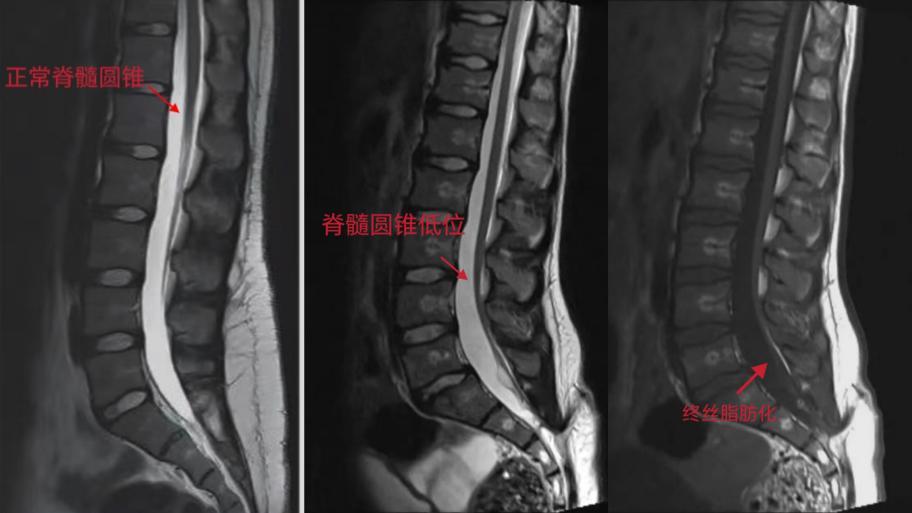

影像学检查是很有必要的,MRI是确诊脊髓栓系的首选方法和金标准,以下是MRI诊断脊髓栓系的几个要点:

1.脊髓圆锥低位:成人低于腰2椎体水平,儿童低于腰3椎体水平。

2.终丝变短、增粗、紧张以及马尾粘连,终丝>2mm。

3.其他相关改变:如椎管内外脂肪瘤、脊柱纵裂,脊髓空洞,椎体畸形以及腰骶部皮毛窦等等。